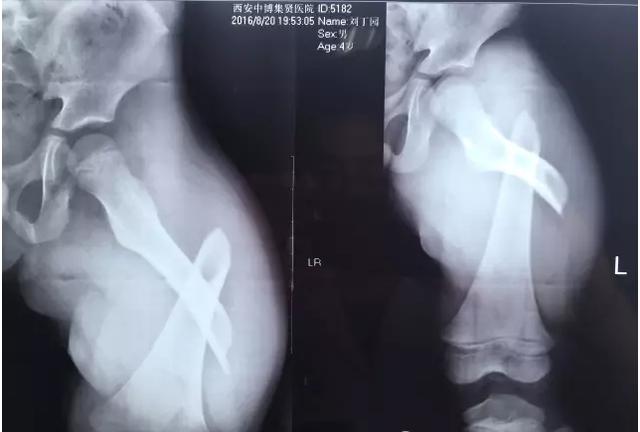

專家表示,大部分骨折是跌倒引起的,最多見的就是骨質(zhì)疏松性骨折,主要包括橈骨遠端、肱骨近端、胸腰椎骨折和髖部骨折。

“許多人跌倒后的第一反應(yīng)是手撐地,導(dǎo)致摔倒的力量經(jīng)手腕傳導(dǎo)至前臂,從而形成橈骨遠端骨折?!北本┓e水潭醫(yī)院新街口院區(qū)創(chuàng)傷骨科副主任醫(yī)師王陶說,如果是髖部骨折,對高齡老人而言,風(fēng)險和危害更大。